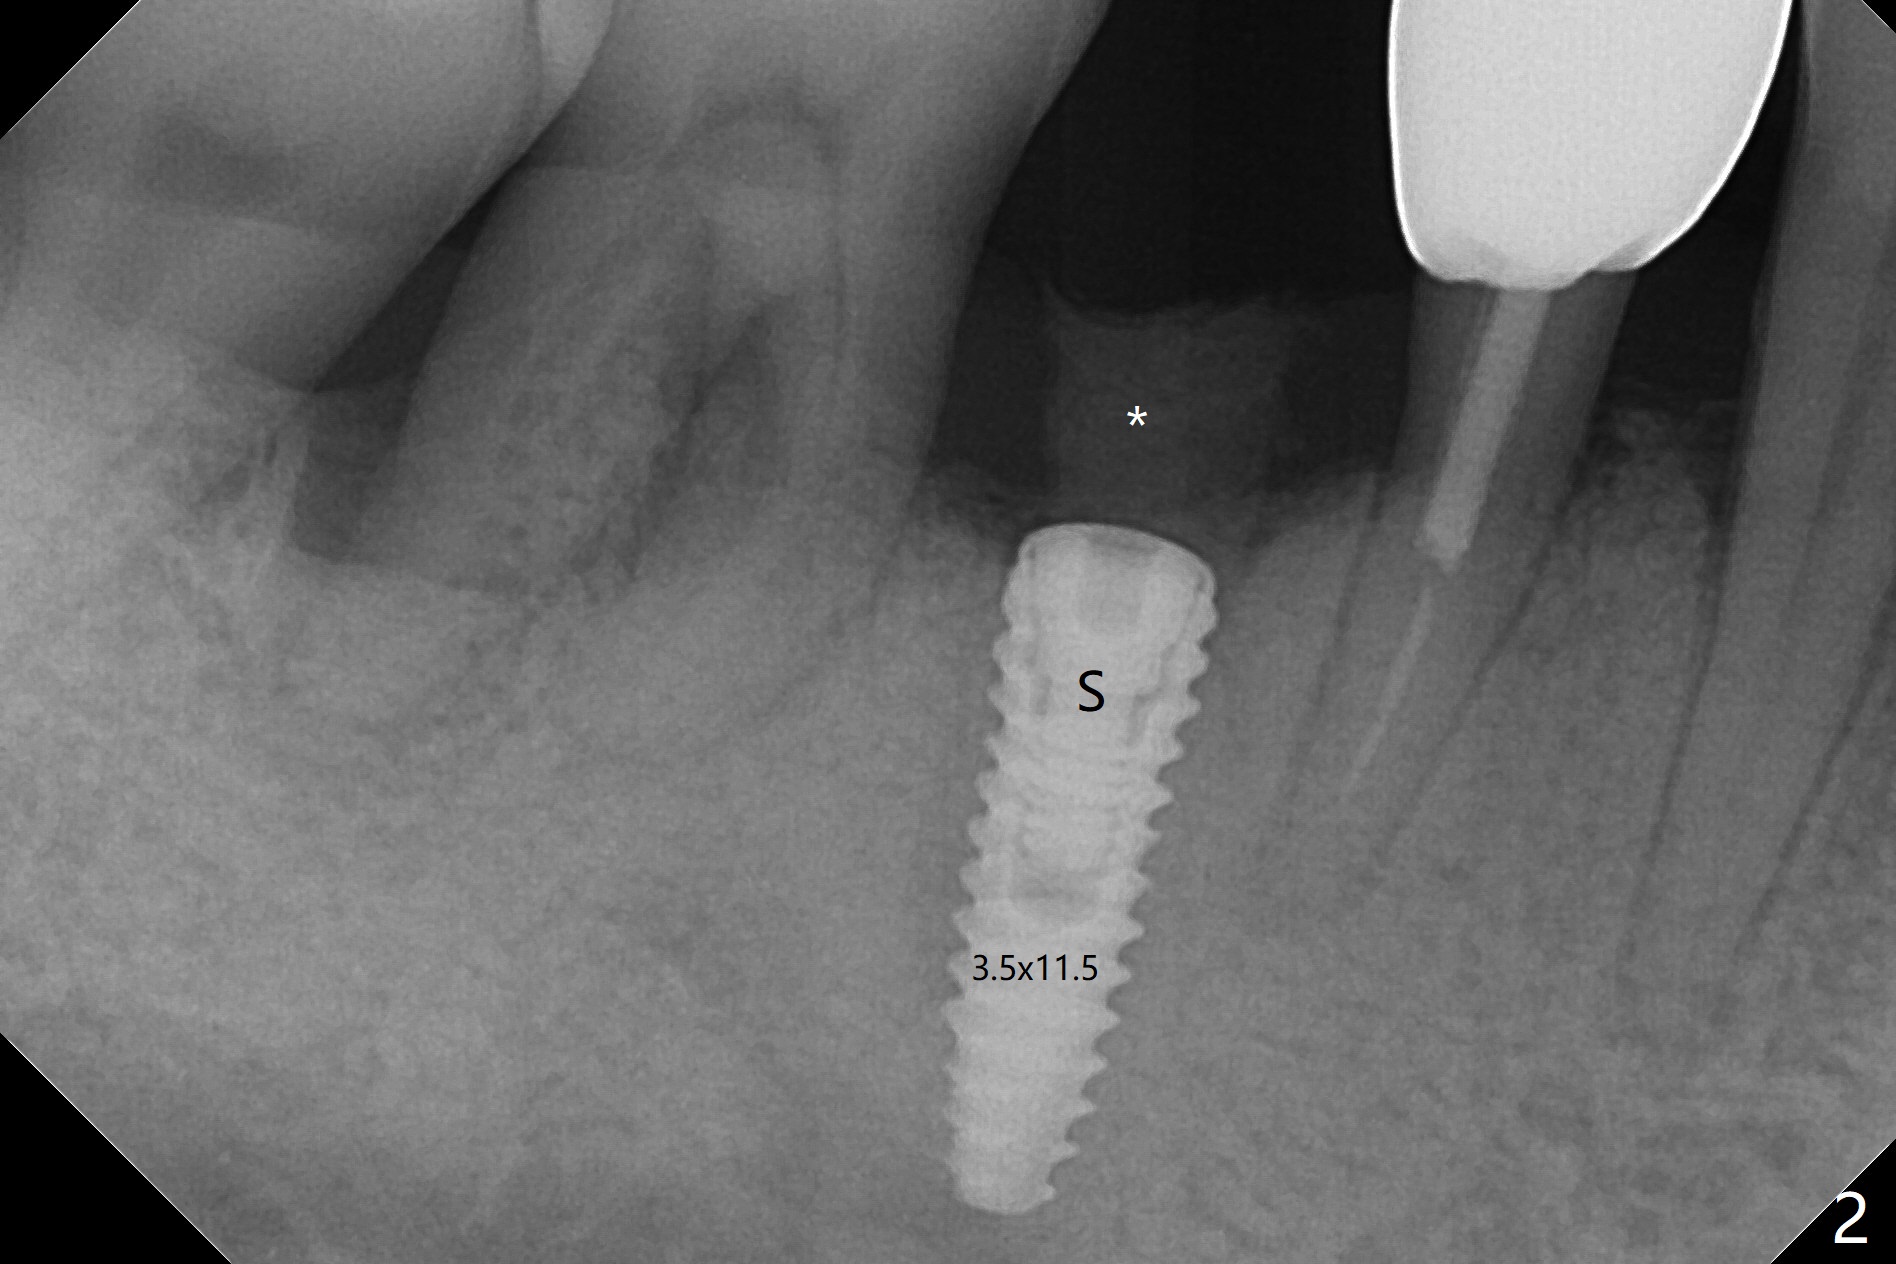

At the time of surgery, there are no 5x10 mm implants in the office for the sites of #14 and 15. Reanalysis of CT shows that there is enough bone for 11.5 mm implants. Before implant placement (Fig.1), there is no perforation of the sinus floor, as shown by probing and nasal blowing test. When a 3.5x11.5 mm implant is placed at #29 in the same appointment, it appears to be supracrestal buccal. Autogenous bone (Fig.2,3 *) is placed in the osteotomy following insertion of a healing screw (S). Periodontal dressing is applied, but it is dislodged after dinner. In fact there is bone coronal to the implant 4.5 months postop (Fig.4), which is confirmed during uncover procedure. There is no abnormality at #14 or 15 4.5 months postop (Fig.5). Impression is taken following extraction of the abnormally shifted opposing tooth #18.